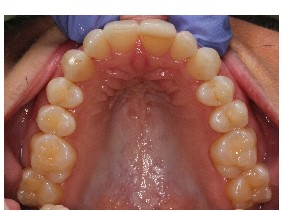

The best age is as soon as it is suspected there are airway issues, our youngest patient is 2.5 years old. The sooner we recognize an airway issue, the greater the chances of achieving harmonious physical and neural growth and development. Below are examples of patients in our practice who have undergone airway development for pediatric sleep apnea or sleep disordered breathing:Adults

We recognize many adults need expansion treatment but that becomes more difficult as we age. Adults with sleep disordered breathing present with many symptoms that can include, snoring, open mouth breathing, sleep apnea, upper respiratory resistance syndrome, and trouble falling or staying asleep. The goal is to determine why these symptoms are present and what can be done to improve the patient’s quality of life with appliances or surgical recommendations. Dr. Kuhta uses specialized bone supported expanders to change the shape of the jaw and not just mask the problem. Every treatment plan is specialized to your needs and aims to alter the way in which you breathe. Dr. Kuhta offer’s non-surgical and minimally invasive surgical options to expand or widen the upper jaw. Using bone-based expanders the goal is to widen the jaw and not just tip the teeth. By expanding the jaw with TAD-based (or mini implant) expanders, you can improve airway, increase room for the tongue, open the nasal cavity and correct crossbites. Skeletal expansion on adults can be life changing! If you are interested in the maxillary skeletal expander (MSE) your next step is scheduling an airway consultation. From there we determine if you are a possible candidate and progress to 3-D imaging to evaluate the probable success of expansion. Before your appointment if you would like to research MSE appliances, Dr. Kuhta would be happy to answer any specific questions.